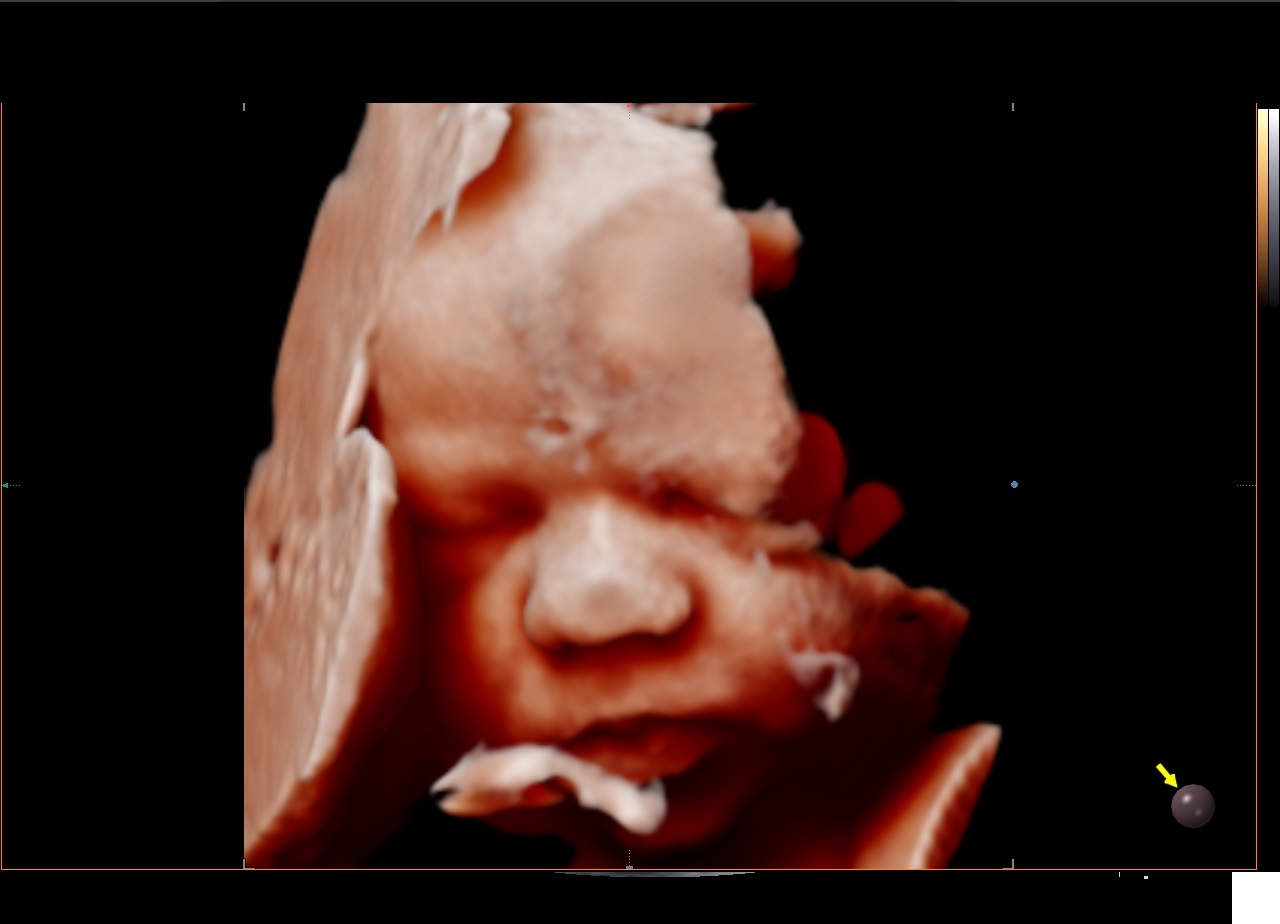

Le RealisticVue™ propose des rendus anatomiques de haute résolution en 3D/4D. Une source lumineuse est modélisée afin de permettre un effet d'ombre sur les structures et de surligner les zones d'intérêt.